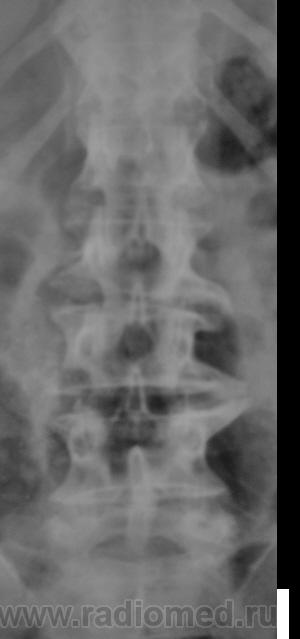

Спондилолистез L5-S1 - истинный, поэтому природа сама набедокуривши, сама и оберегает. Трудно представить безсимптомное течение, если бы это было последствием травмы. Очень рад, что Андрей Юрьевич приводит выдержки из Рейнберга. Судя по желтизне страниц - это первое издание.

По данному случаю:на мой взгляд, он является примером того, что попытки обяснить клинику(страдания пациента) только изменениями на R-граммах несостоятельны (если бы, у пациентки были жалобы,скажем на боли в области поясницы, сделали бы вывод-"что вы хотите?!-деформирующий спондилёз, да ещё спондилолистез- из-за этого и болит"). Думаю, многие сталкивались такими направлениями: "Направляеться на R-графию пояснично-крестцового отдела позвоночника.D.S.:Исключить остеохондроз ".

А во сколько лет человек заимел все -озы? И спондилолиз с листезом 2 ст?

Спондилолистез L5-S1 - истинный, поэтому природа сама набедокуривши, сама и оберегает. Трудно представить безсимптомное течение, если бы это было последствием травмы. Очень рад, что Андрей Юрьевич приводит выдержки из Рейнберга. Судя по желтизне страниц - это первое издание